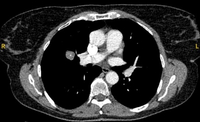

Computed tomography (CT) sections from two cases with benign perifissural nodules. Note the smooth margins and the normal undisturbed adjacent fissure

From the collection of Dr George Tsaknis, MD, PhD, FRCP(London), MRQA, MAcadMEd, PGCert; used with permission